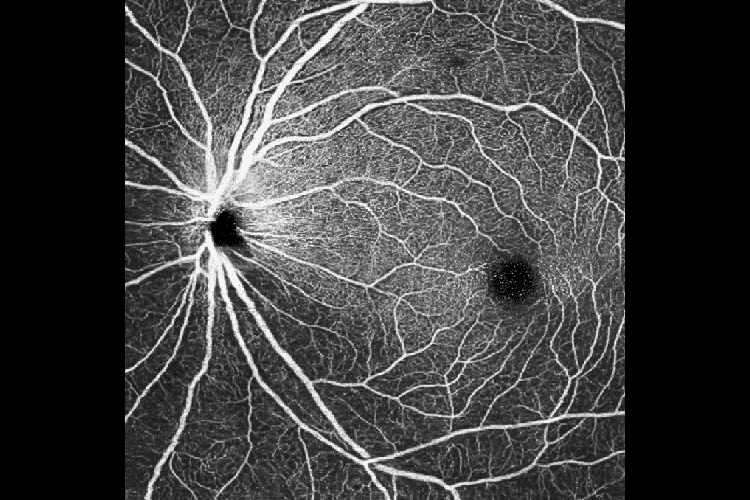

ОКТ Ангіографія з ANGIO Expert

Функція інтелектуального усунення шумів Canon на основі штучного інтелекту пропонує нову якість зображень ОКТА на основі лише одного сканування – без необхідності отримувати та об’єднувати кілька зображень. Технологія Canon Deep Learning — це революційна технологія, яка базується на величезних обсягах клінічних даних для отримання зображень із значно зменшеним шумом зображення, підвищеною деталізацією та покращеною видимістю всього за кілька секунд.